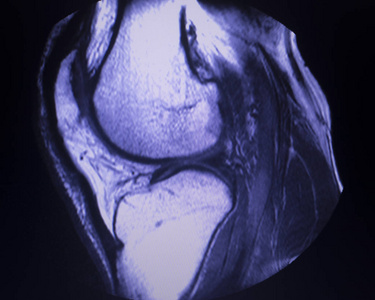

怎么看半月板撕裂的磁共振片

图片尺寸1984x1488